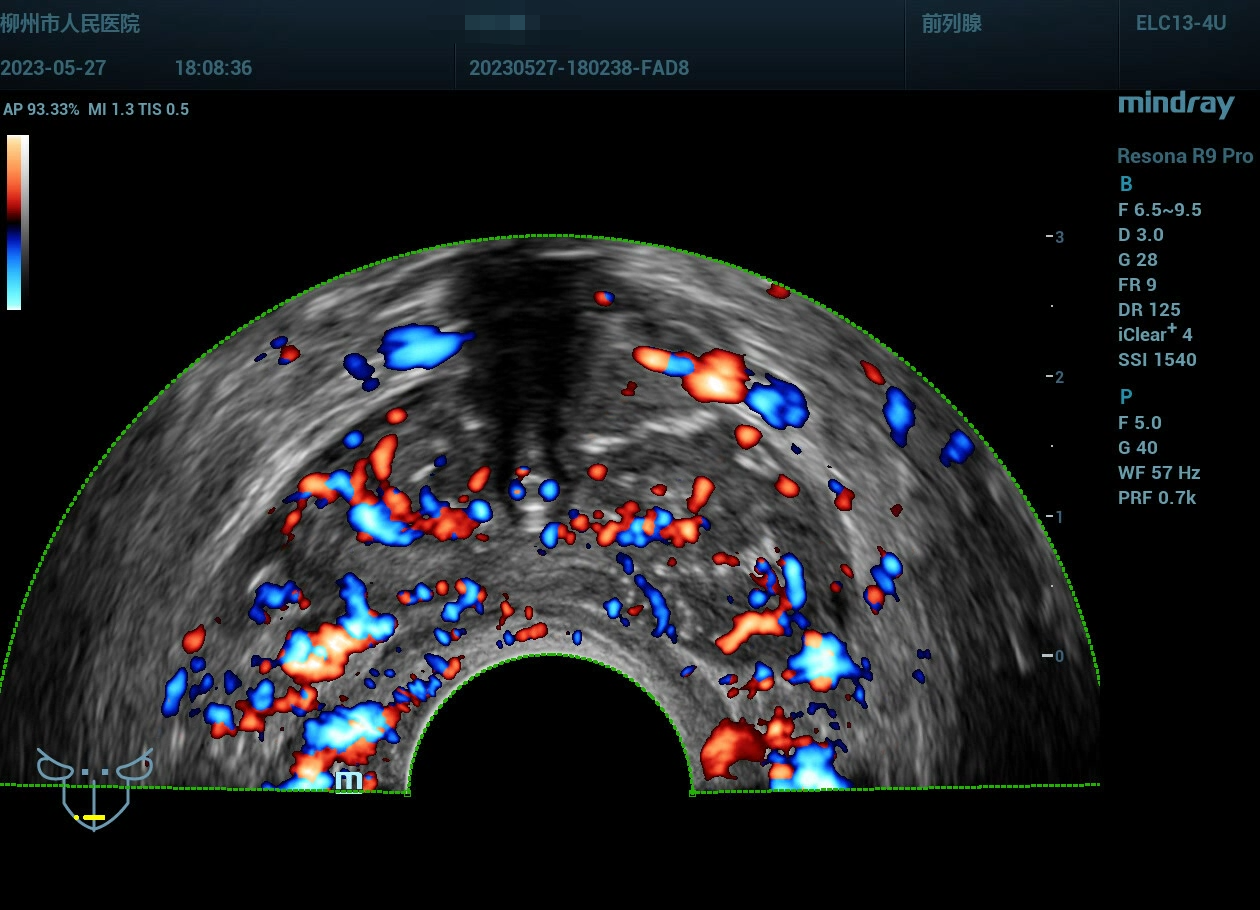

经会阴前列腺穿刺,病例实操(前列腺癌),柳州市人民医院,2023年

老年男性

经会阴前列腺穿刺,病例实操(前列腺癌),柳州市人民医院,2023年-主页丨今日超声